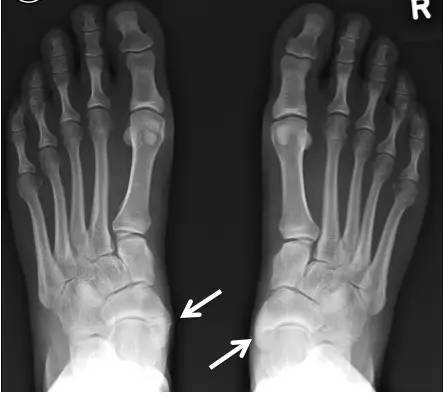

足副舟骨是发生在舟骨结节第二骨化中心的先天性变异。大约有10-15%的人会存在足副舟骨。

足副舟骨是人体最大的副骨,可分为3型。

一型不与舟骨相连,一般无症状。

二型副舟骨是舟骨的一部分,由结节部纤维软骨板分开。进一步分为2A和2B型。

三型二者有骨桥连接,形成角状舟骨。

当发生足副舟骨疼痛时,首先要拍X光确诊,并确定分型。